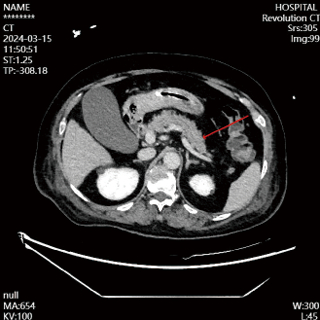

入院第4天,患者神志尚未转清,有自主睁眼,但对呼喊无反应,对疼痛刺激有局部屈曲反应,查体腹软,左上腹触诊患者有明显疼痛刺激反应,复查腹部CT(见图 2),提示胰腺体下方渗液明显增加,改良的CT严重指数评分(modified CT severity index, MCTSI)4分。动态复查血清淀粉酶及脂肪酶,尽管胰酶指标仍在正常范围,修正临床诊断:AP。调整治疗,在之前胃肠道功能支持治疗基础上,加用生长抑素抑制胰液分泌。治疗3 d后复查腹部增强CT(见图 3),胰腺无坏死,胰周渗液明显吸收,MCTSI 2分,逐步减停生长抑素。

| 图 3 2024-03-15患者胰腺形态及强化未见明显异常 |